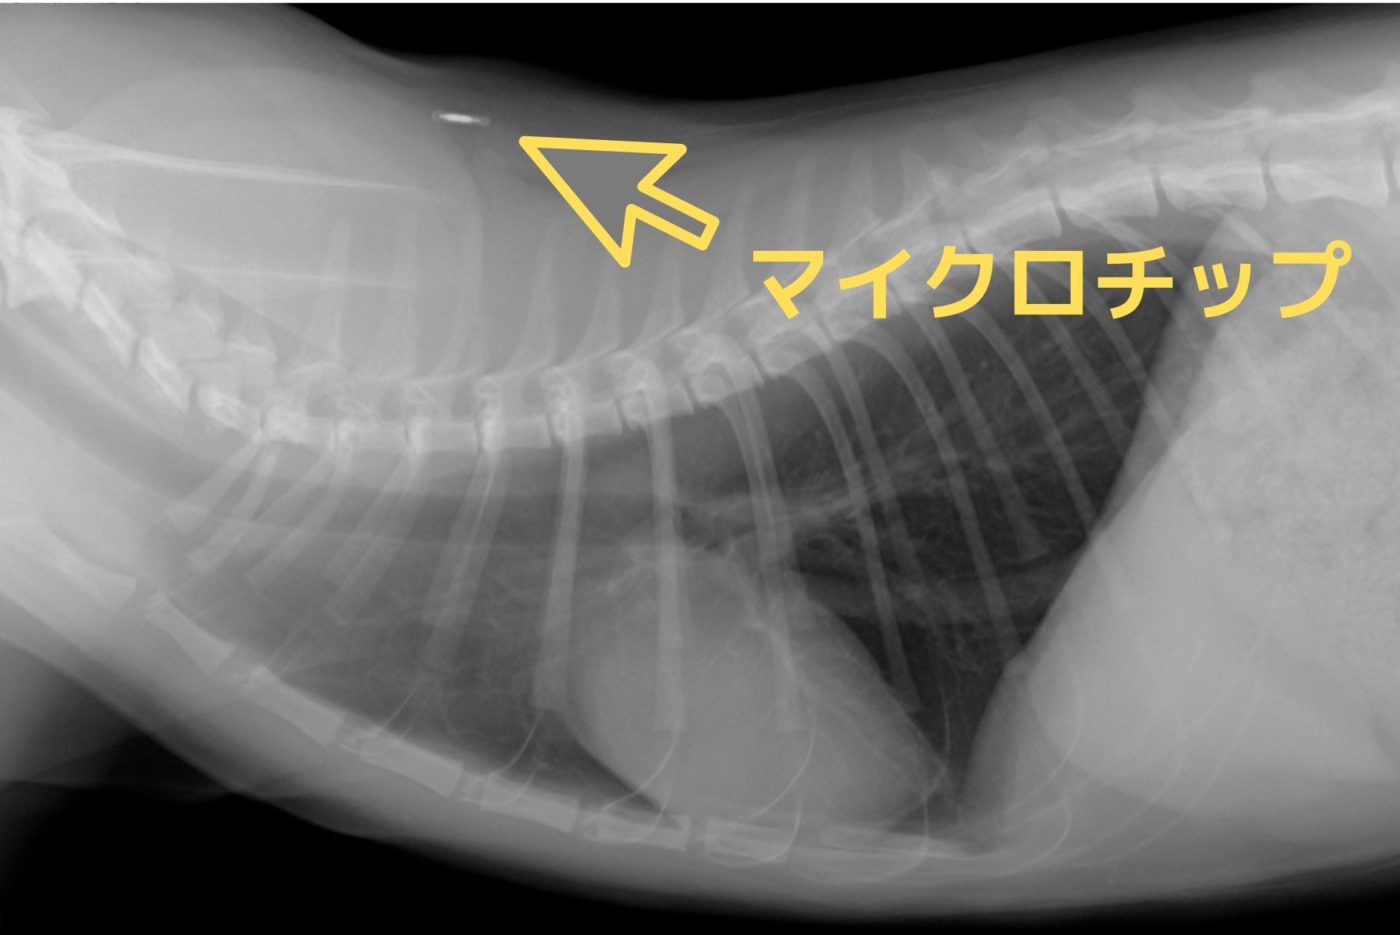

マイクロチップは直径約2ミリ、長さ約8~10ミリの円筒状をしていて、特殊な注射器で背中の皮膚の下に挿入します。

獣医師が使い捨ての専用注射器を使い、背中の皮下に埋め込みます。

マイクロチップを装着したところに大きな傷などはできません。

しかも触ってもどこに埋め込まれたか分かりません。

(余程痩せているか、薄い皮膚のところに埋め込まれた場合など、まれに気付くこともありますが・・・)